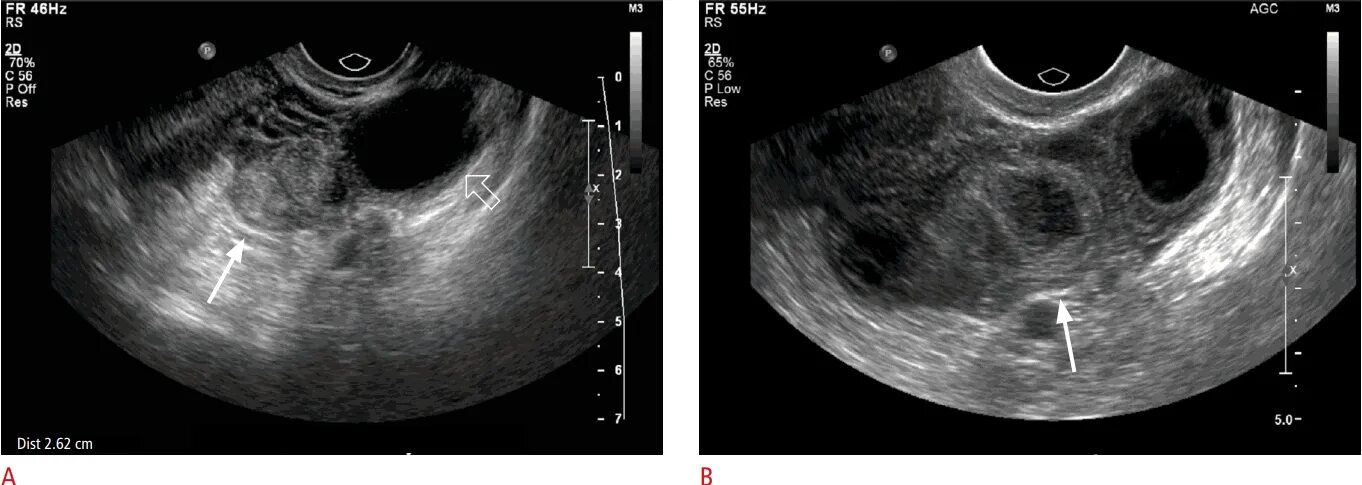

Можно ли на узи увидеть внематочную беременность